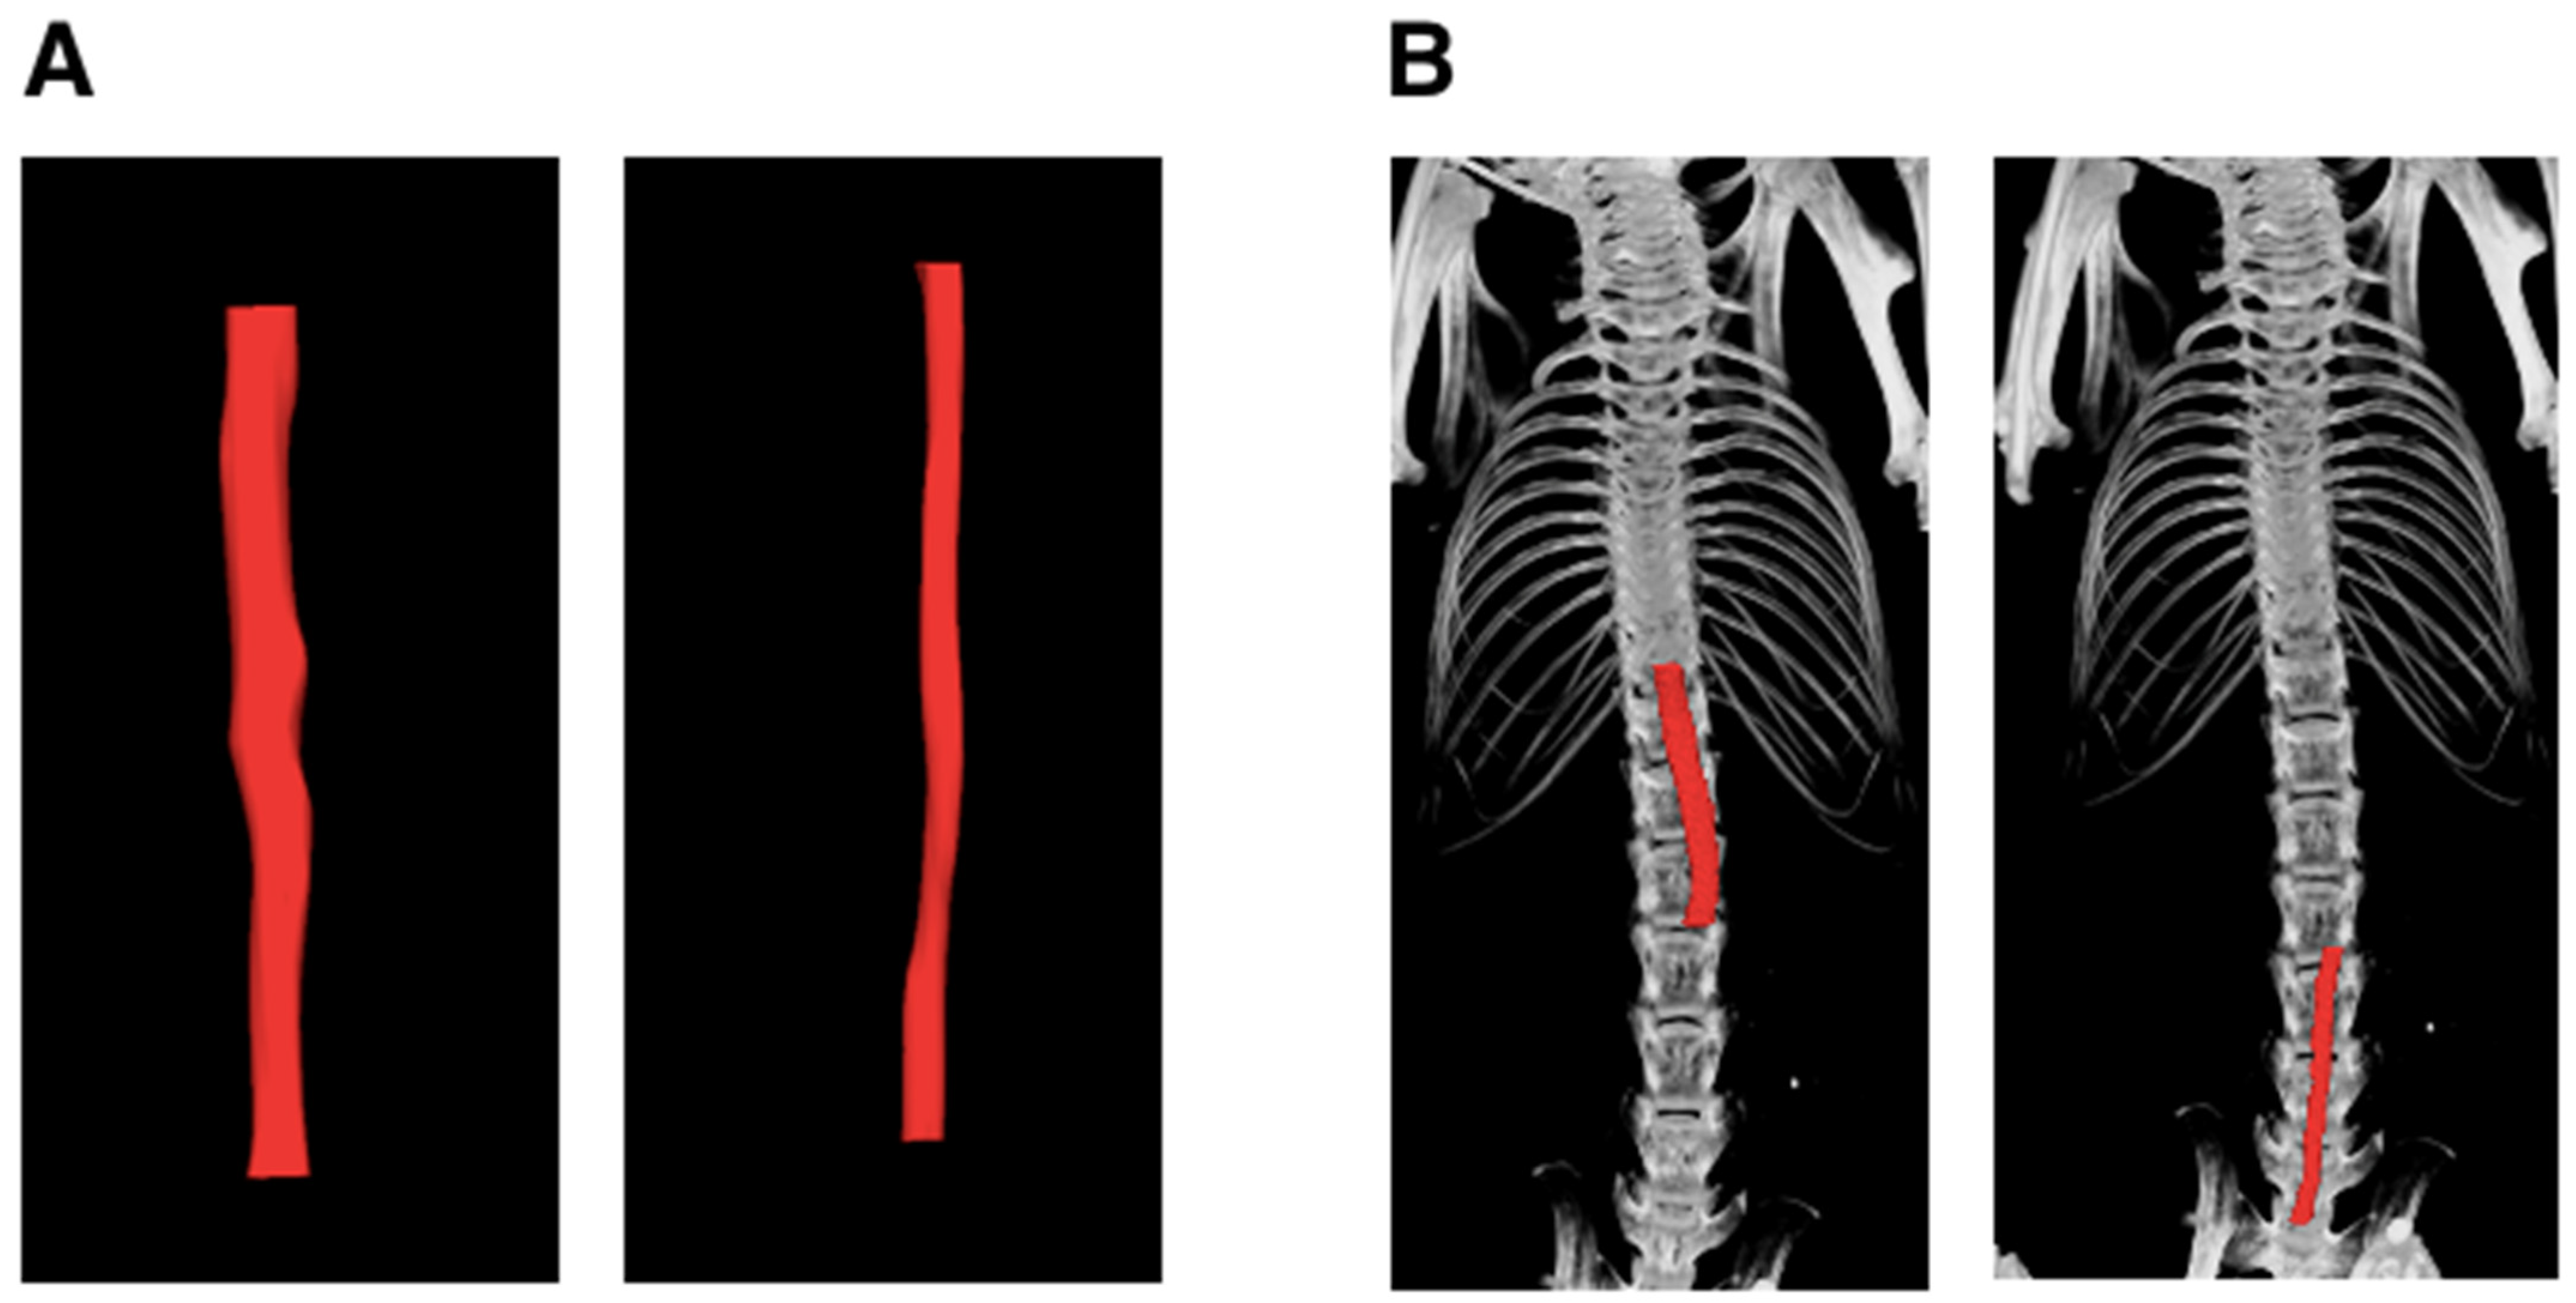

Aortic volume comparisons between μCT and USS in mice indicated that μCT tends to yield larger measurements than USS for both suprarenal and infrarenal segments. Example images of USS reconstruction in mice are shown in Figure 4. The mean differences were 0.59 mm3 (suprarenal) and 0.67 mm3 (infrarenal), but these were not statistically significant, with p-values of 0.32 and 0.16, respectively. Moderate positive correlations were observed in both segments (R2 = 0.45), suggesting a consistent but not strong relationship between the μCT and USS measurement techniques (Figure 5 and Figure 6). The measurements of aortic volume in the supra- and infrarenal aorta, obtained using both USS and μCT, are reported in Table 1.

Figure 4.

Steps of ultrasound (USS) three-dimensional lumen volume measurement (3DLV) reconstruction of the suprarenal and infrarenal aorta. (A) Cube view of the infrarenal aorta, (B) cross view, (C) surface view, and (D) overlay view.

Images of suprarenal and infrarenal aortas reconstruction in (A) ultrasound (USS); suprarenal (left) and infrarenal (right) and (B) micro-computed tomography (μCT); suprarenal (left) and infrarenal (right).